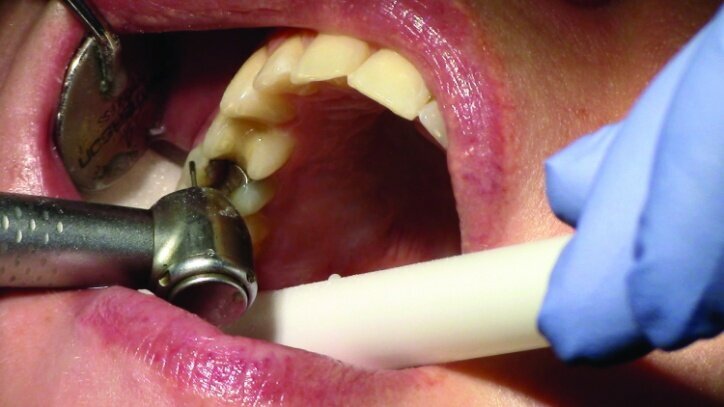

Depth guide cuts were made using a 330 bur, which has a 2 mm cutting surface (Figs. 2a–3b). This ensures 2 mm of occlusal reduction to accommodate 2 mm of material thickness on the occlusal surface of the restoration.

Gross occlusal reduction was completed using a KS7 bur to the depth cuts (Figs. 4–8b, 9c). Adequate clearance was verified with a 2 mm prep check from Common Sense Dental Products.

The remainder of the existing composite resin in #3 and the amalgam in #4 were removed. The occlusal surfaces of the preparations were blended into the interproximal areas using a KS2 bur to create smooth preparations (Figs. 10–15c). There was no retention or resistance form prepared to retain the restorations.